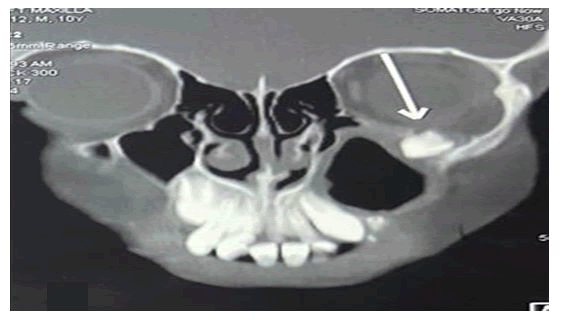

A contrast enhanced Computed Tomography (CT) of nose and paranasal sinuses was done which showed presence of ectopic tooth at the level of floor of left orbit with mucosal thickening along walls of left maxillary sinus (Figure 2).